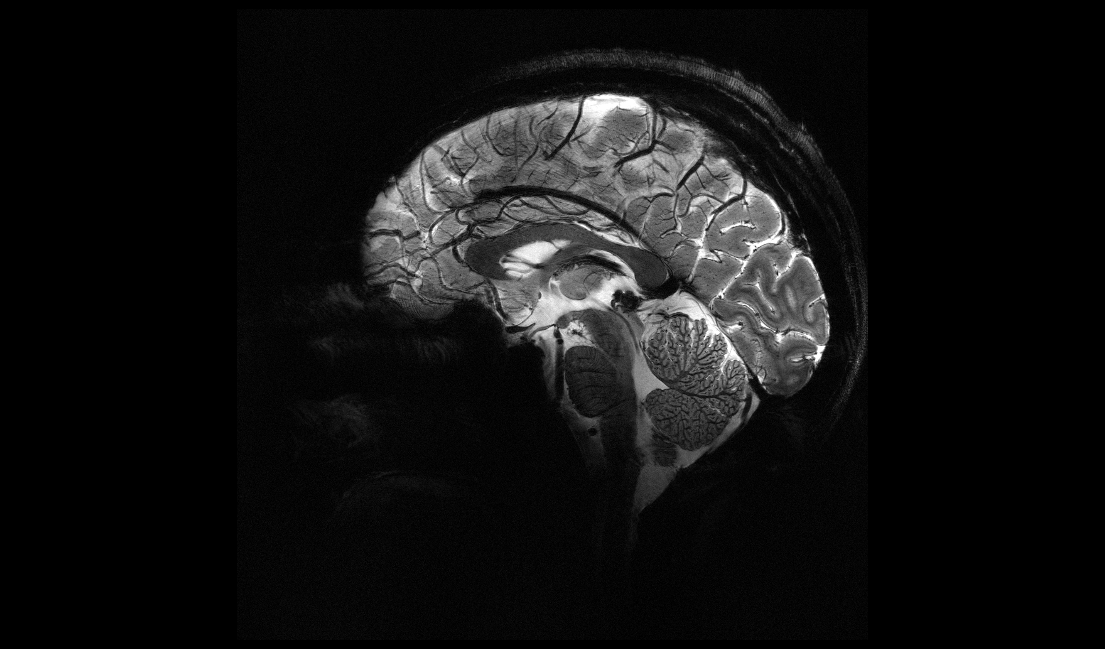

ResourcesVendorsAdvanced Visualization3D SoftwareSiemens Healthineers51 Valley Stream Parkway40 Liberty Boulevard Malvern, PA, USA 19355-1406eMail:Website:https://www.medical.siemens.comPhone:888-826-9702Latest from Siemens HealthineersClinical NewsSiemens posts strong revenues for Q4, fiscal year 2024By AuntMinnieEurope.com staff writersSiemens Healthineers posted strong revenue growth in the fourth quarter and full fiscal year of 2024 compared with last year.November 7, 2024Industry NewsSiemens posts revenue, earnings growth in Q3By AuntMinnieEurope.com staff writersStrong performance in its Varian and Diagnostics business segments propelled Siemens Healthineers to 7% comparable revenue growth in its third quarter.July 31, 2024Molecular ImagingSwiss team shows ultralow dose PET can avoid need for CTBy Kate Madden YeeAn ultralow dose imaging method used with long axial field-of-view PET scanners produces images with a radiopharmaceutical dose 50 times lower than the standard effective dose.June 13, 2024InterventionalSiemens, World Stroke Organization sign 2-year stroke care dealBy AuntMinnieEurope.com staff writersSiemens Healthineers and the World Stroke Organization have signed a two-year partnership agrement to improve global access to stroke care.June 10, 2024UltrasoundSiemens launches cardiac ultrasound applicationsBy AuntMinnieEurope.com staff writersSiemens Healthineers has launched new cardiology AI applications for its Acuson Sequoia ultrasound system.May 31, 2024Digital X-RayAI functions in x-ray systems may save radiographers timeBy Will MortonIntelligent virtual and AI-based collimation features appear to save radiographers time during x-ray image acquisitions, a new study has found.May 24, 2024MRISiemens begins construction on DryCool facility, MRI magnet plantBy AuntMinnieEurope.com staff writersThe new facility is one of six current and planned Siemens Healthineers manufacturing sites in the U.K., according to Siemens.May 10, 2024Artificial IntelligenceAI stroke software differences don't affect thrombectomy eligibilityBy Liz CareyThe research findings suggest, however, that scanner model and local CT perfusion protocols can influence performance and cause discrepancies.May 10, 2024Industry NewsSiemens reports revenue, profit gains in Q2By AuntMinnieEurope.com staff writersSiemens Healthineers is highlighting revenue and earnings growth for its 2024 fiscal second quarter.May 7, 2024MRIFrench-led team unveils 11.7 tesla MRI scans of human brainBy Philip WardA research group based in Saclay, near Paris, has taken the wraps off what it claims are the world's first MRI scans of the human brain in vivo taken at a field strength of 11.7 tesla. President Macron has congratulated the researchers.April 3, 2024CTBerlin team unveils progress on photon-counting CTBy Liana GruenbergScientists are moving ahead with research studies using a photon-counting CT unit installed last summer at a contrast media laboratory. Preclinical trials have been carried out.March 26, 2024ECR 2024Siemens unveils Magnetom Flow MRI scanner at ECR 2024By Erik L. RidleyA new 1.5-tesla MRI scanner with very low helium requirements took center stage for Siemens Healthineers at ECR 2024.February 29, 2024Artificial IntelligenceRadiologists in Europe ramp up testing of AIBy Will MortonFour out of seven commercially available AI algorithms for detecting lung nodules on x-rays performed better than human readers in a recent study.January 12, 2024Molecular ImagingNew portable PET scanner tested in humansBy Will MortonBrain imaging with a newly developed portable PET scanner appears feasible, with a comparison to conventional PET imaging revealing similar results in human subjects.December 29, 2023CTSiemens launches Somatom Pro.Pulse CT scannerBy AuntMinnieEurope.com staff writersSiemens Healthineers is launching a new dual-source CT scanner, Somatom Pro.Pulse.November 20, 2023